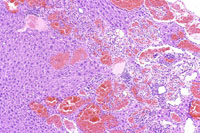

Dilated vascular spaces have replaced hepatic parenchyma in this hemangioma. High magnification shows dilated vascular spaces lined by flattened and sometimes dome-shaped endothelial cells and mild atrophy of the visible hepatic cords.